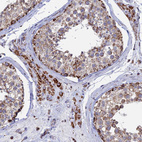

Immunohistochemical staining of human rectum shows strong granular cytoplasmic positivity in glandular cells.